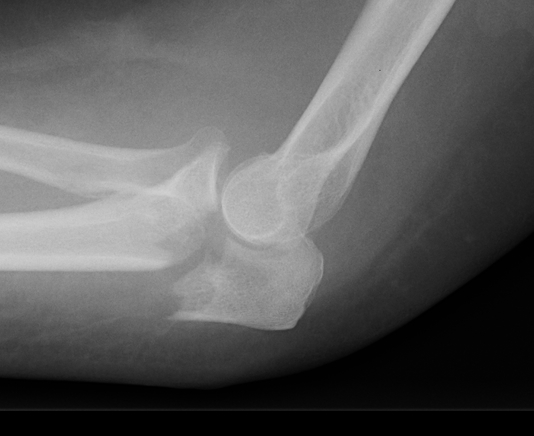

Mayo Classification

A: Non comminuted

B: Comminuted

| Type I | Type II | Type III |

|---|---|---|

| Minimally displaced | Displaced | Trans-olecranon fracture dislocation |

| 10% | 85% | 5% |